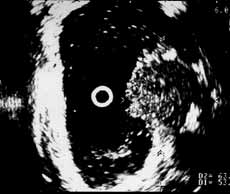

Рис. 5 и 6. Цистэндосонограммы. (Слева) Рак мочевого пузыря стадия Т2в. (Справа) Рак мочевого пузыря стадия Т3а. Мышечная стенка полностью разрушена.